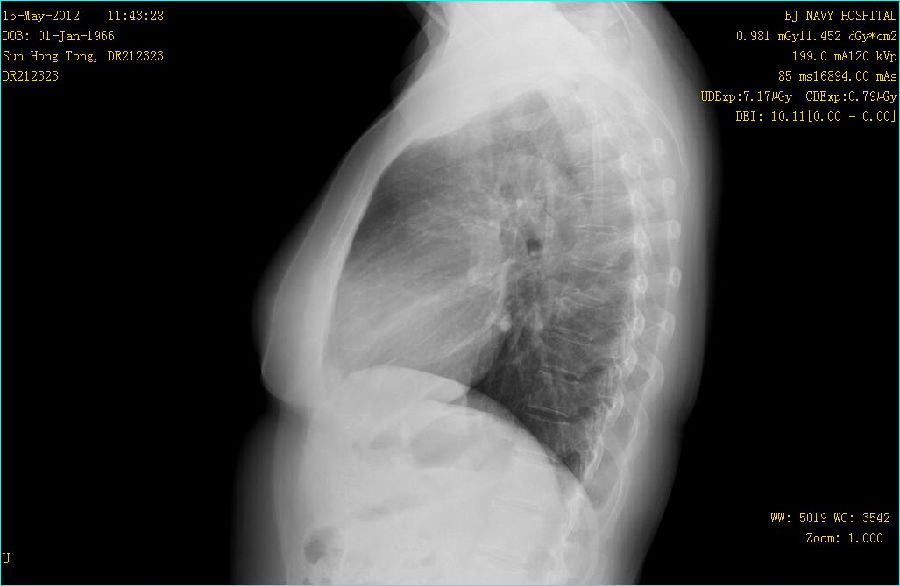

双能成像图片:

病例点评: GE公司的双能成像检查采用可以快速读取的X线平板探测器,由X射线球管间隔约150ms进行低能(低kVp)和高能(高kVp)两次曝光。采集到的图像经过图像工作站快速处理产生一组3幅图像:标准平面图像,软组织图像和骨骼(钙化)组织图像。这种双能量DR检查对于改善肋骨后面重叠区域的非钙化结节的能见度非常有效。同时对在肋骨间和超过骨组织钙化的结节能更好地显示。